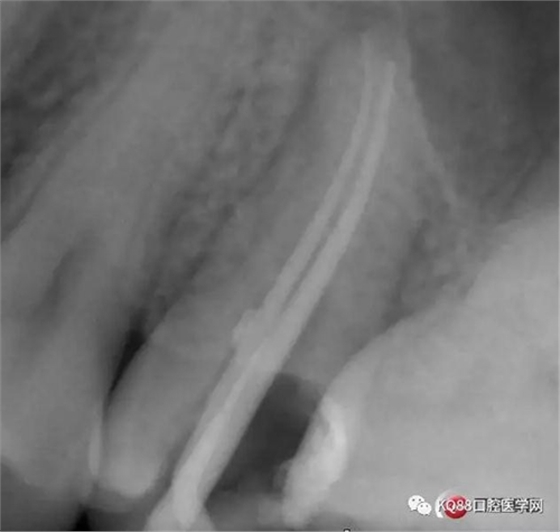

Y形態(tài)變形成了,根間支也明顯出現(xiàn),充填嚴(yán)密,雖然根管治療的成功率不是一百,但是我們盡可能把那一點(diǎn)做到位,往往結(jié)果可能會很驚人,如果我在第一次就充填了,可能也不會有什么錯誤,但是態(tài)度就已經(jīng)輸了,我們基層做根管不會像武大等那么規(guī)范,但是也希望可以向其靠攏,一個好的根管,上面才能有美的修復(fù)。

四個根管成型,只是近中兩個根管融合為一個,典型的C型根管。最后開始根充,射片。

充填完成。以此兩例根管治療,說明的并不是完全技巧,更多的是態(tài)度,我的根管治療做的并不是很好,但是我一定會把態(tài)度端正起來,希望同行們都能一起加油,利用手上最基本的設(shè)備,用心做好每一個根管。如有錯誤,請多指證,謝謝!